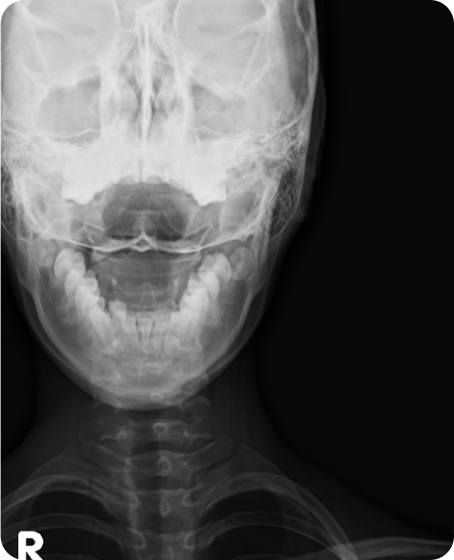

▲ 치료 전 (2016년 1월 21일)

▲ CTA 5개월 착용 (2016년 6월 29일)

▲ CTA 9개월 착용 (2016년 10월 29일)